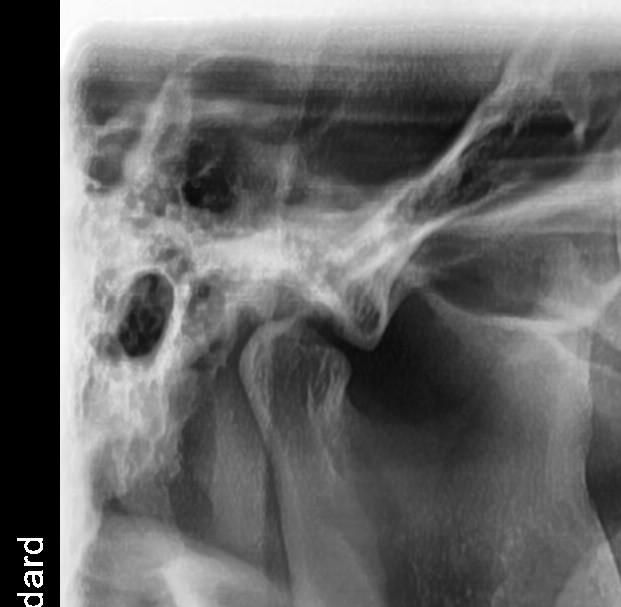

씹을 때 턱이 아파요 턱 과두 한 번 봐주세요

약간 단단한 거 먹을 때 턱이 아픈데요 지금 현재 상태가 병원에가서 치료 받아야 할 정도인가요?

몇 달 전부터 증상이 시작 됐는데 확인 한번 부탁드립니다

왼쪽 턱관절의 condyle 모양이 다소 각이져 있긴 한데 심한 턱관절염으로 보이진 않습니다. 딱딱한 음식 피하시고, 턱 마사지 해주세요 증상이 그래도 지속되면 구강내과 가보세요